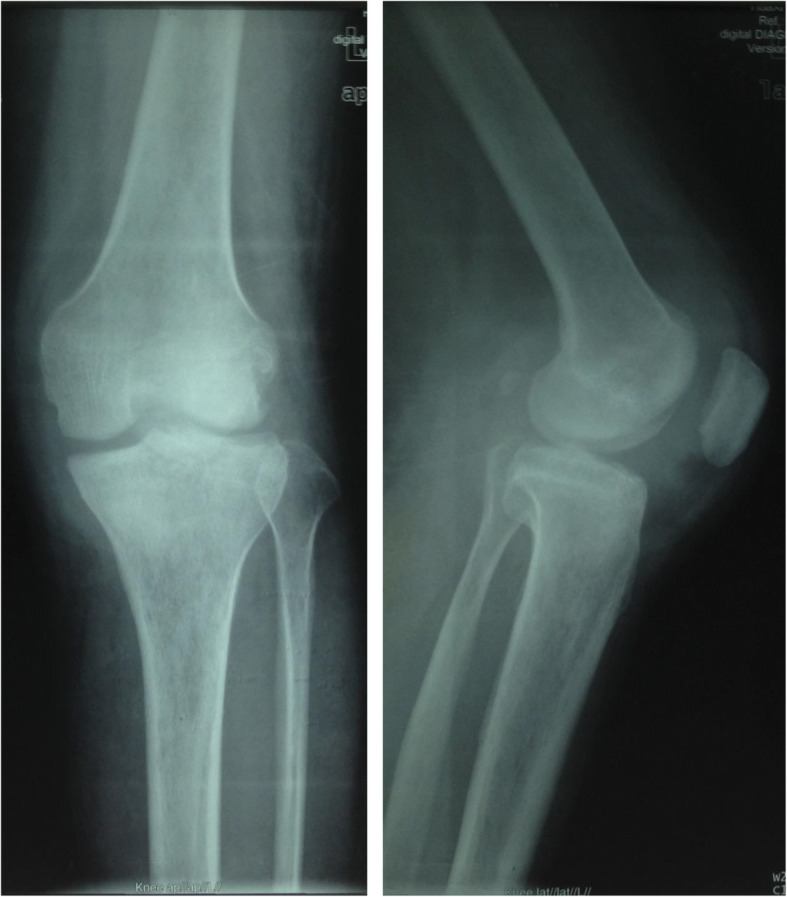

Fig. 1.

X-ray (anteroposterior and lateral): clearly osteoporosis, uneven joint space narrowing, and joint bone destruction